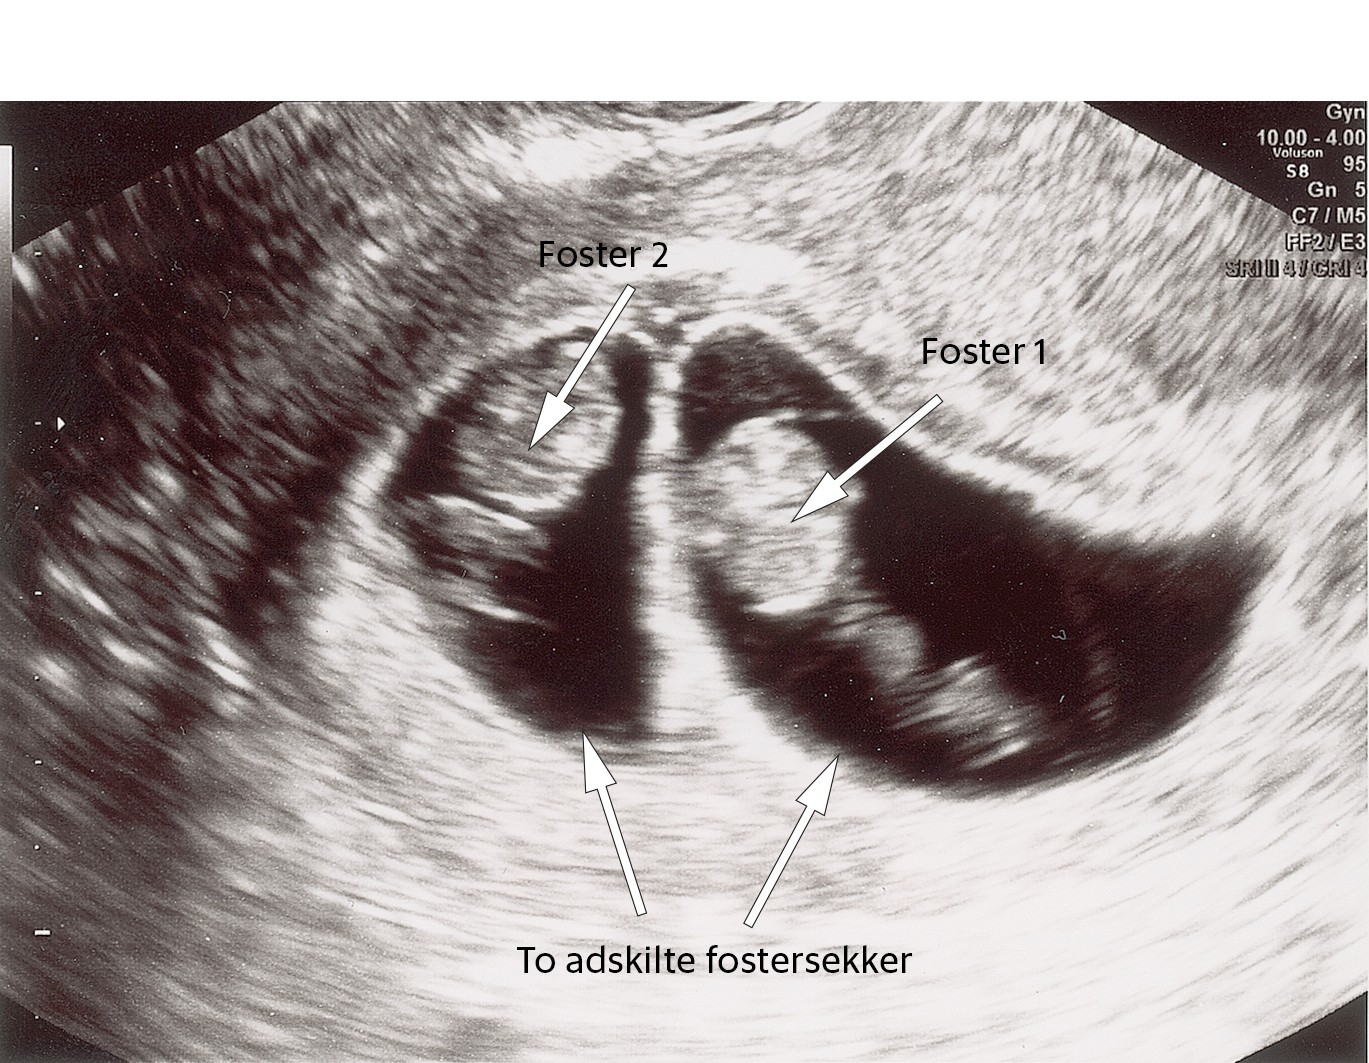

Ved fryseforsøket ble kvinnen behandlet med aromatasehemmeren letrozol for å fremme optimal eggløsning (1). Det ble utført transvaginal ultralydundersøkelse et par dager før forventet eggløsning, hvor man så to preovulatoriske follikler. Kvinnen fikk positiv eggløsningstest, og embryoet ble tint og satt inn i livmorhulen. Graviditetstesten et par uker senere var positiv. Paret kom derfor til ultralydundersøkelse i svangerskapsuke 8. Både de blivende foreldrene og den undersøkende legen ble overrasket da man så to adskilte fostersekker, hver med ett vitalt foster. Som bildet viser forelå en diamnional, dikorial tvillinggraviditet.